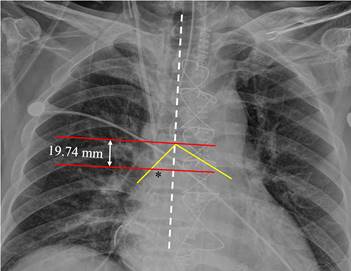

The primary end point was the optimal insertion depth, and we placed the catheter tip 2 cm above the superior edge of the crista terminalis using real-time TEE. The secondary endpoint was a new formula with the most correlated patient parameters to predict the optimal depth for central venous catheterization through the right internal jugular vein. Next, we calculated the accuracy of the new formula and some previous guidelines for placing the tip of the inserted catheter within the newly proposed optimal zone (from 1 cm above to 3 cm above the superior edge of the crista terminalis) in the present study and compared the accuracy rate between our new formula and the previous guidelines in terms of the placement of the central venous catheter within the optimal zone. Additionally, we evaluated the vertical distance from the catheter tip to the carina in the postoperative chest X-ray (fig 2).

Figure 2

The vertical distance from the catheter tip to the carina measured on postoperative chest X-ray. On the day after the operation, we measured the distance from the catheter tip to the carina using the following steps. Step (1); we drew a vertical line (the white dotted line) parallel to the patient's spine. Step (2); we drew two horizontal lines at the level of the catheter tip and at the level of the carina (red lines) perpendicular to the vertical line. Step (3); we measured the vertical distance between the two horizontal lines. The intersection point of the two yellow lines represents the carina. The asterisk indicates the tip of the central venous catheter.

A total of 89 patients were enrolled in this trial. Central venous catheterization was successful with the study protocol in all patients. There were no complications in the study. Table 1 shows the diagnosis and types of surgery of the 89 patients participating in the present study. The optimal depth of the catheter to the optimal point, which was 2 cm above the superior edge of the crista terminalis, was 14.5 ± 1.6 cm (95% confidence interval; 14.2 cm to 14.8 cm) under real-time ultrasound transesophageal echocardiography. The distance from the ideal depth point to the carina on postoperative chest X-ray was -1.3 cm ± 1.6 cm (95% CI; -1.0 cm to -1.7 cm); a negative value means that the catheter tip was lower than the carina. The correlation coefficients between the optimal depth and patient parameters, including sex, age, height, weight, and BMI are presented in table 2. Among the variables, patient height was most correlated with the optimal depth.